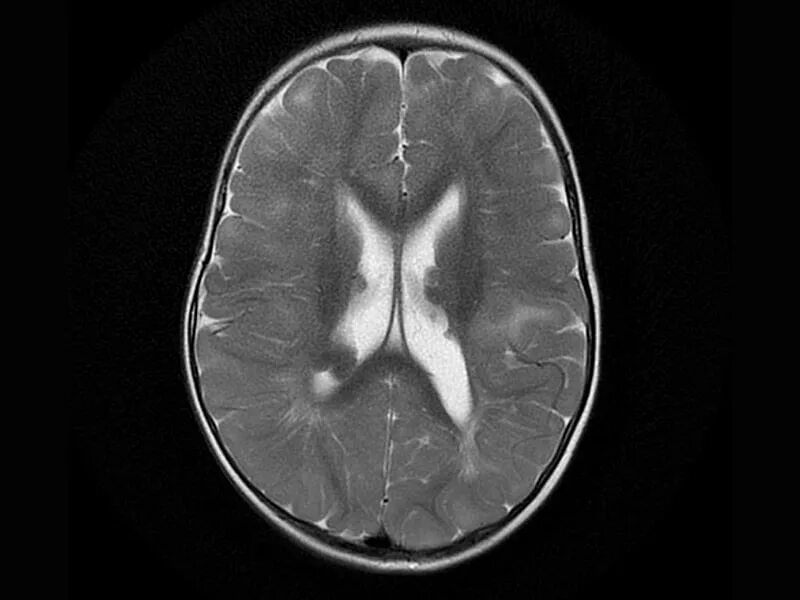

Туберкулезный склероз